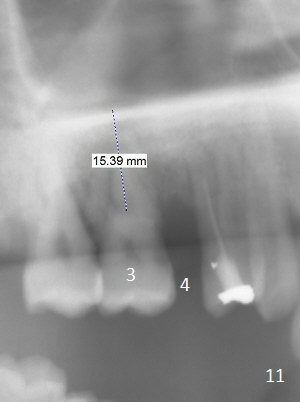

A 36-year-old man (ex-smoker) has advanced chronic periodontitis (Fig.1-5). His chief complaint is "I cannot chew on the right side now because of pain (Fig.1: #3 abscess <) and the bottom front teeth are loose (Fig.2,5: #23-26)". He has not masticated on the left side because of the mobile teeth. Due to finance, implants will be placed at #3,4 (Fig.12), 23 and 26 at the appointments of scaling & root planing.

Class II Division II malocclusion (Fig.2,6) will make it difficult to restore #23-26 implant-supported FPD. Although the teeth #7-10 may need to be replaced later (Fig.7,8), enameloplasty will be conducted for #7-10 (Fig.9 white area; Fig.12 black circles (gross reduction)) prior to #23-26 extraction and implant placement (Fig.10). To be flexible in restoration (angulation) and possible future hybrid denture, 2-piece narrow implants will be placed (3.0 or 3.3 mm) instead of 1-piece ones. In fact CBCT shows that the narrowest regular implant (3.8 mm) can be placed in the lower anterior region (Fig.13-15).